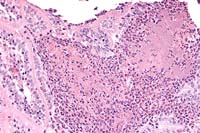

Case 23-2. Intestine. Focal mucosal necrosis with a myriad of ill-defined bacteria appearing as a basopilic haze, surrounded by neutrophils. 20X

Contributor's Diagnosis and Comments: Multifocal subacute purulent enteritis with associated microcolonies of coccobacilli.

There were scattered microabscesses around bacterial colonies in the lamina propria. Some villi were necrotic with eroded or ulcerated mucosa. Occasional mild crypt abscesses were present.

AFIP Diagnosis: Small intestine: Enteritis, necrotizing, neutrophilic, acute, multifocal, moderate, with crypt abscesses, transmural edema, and bacterial colonies, Jersey, bovine.